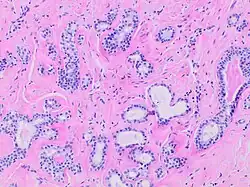

Human submandibular gland. At the right is a group of mucous acini, at the left a group of serous acini.

Histopathology of sclerosing adenosis of the breast.

Adenosis is any disease of a gland. The diseased gland has abnormal formation or development of glandular tissue which is sometimes tumorous.[4]